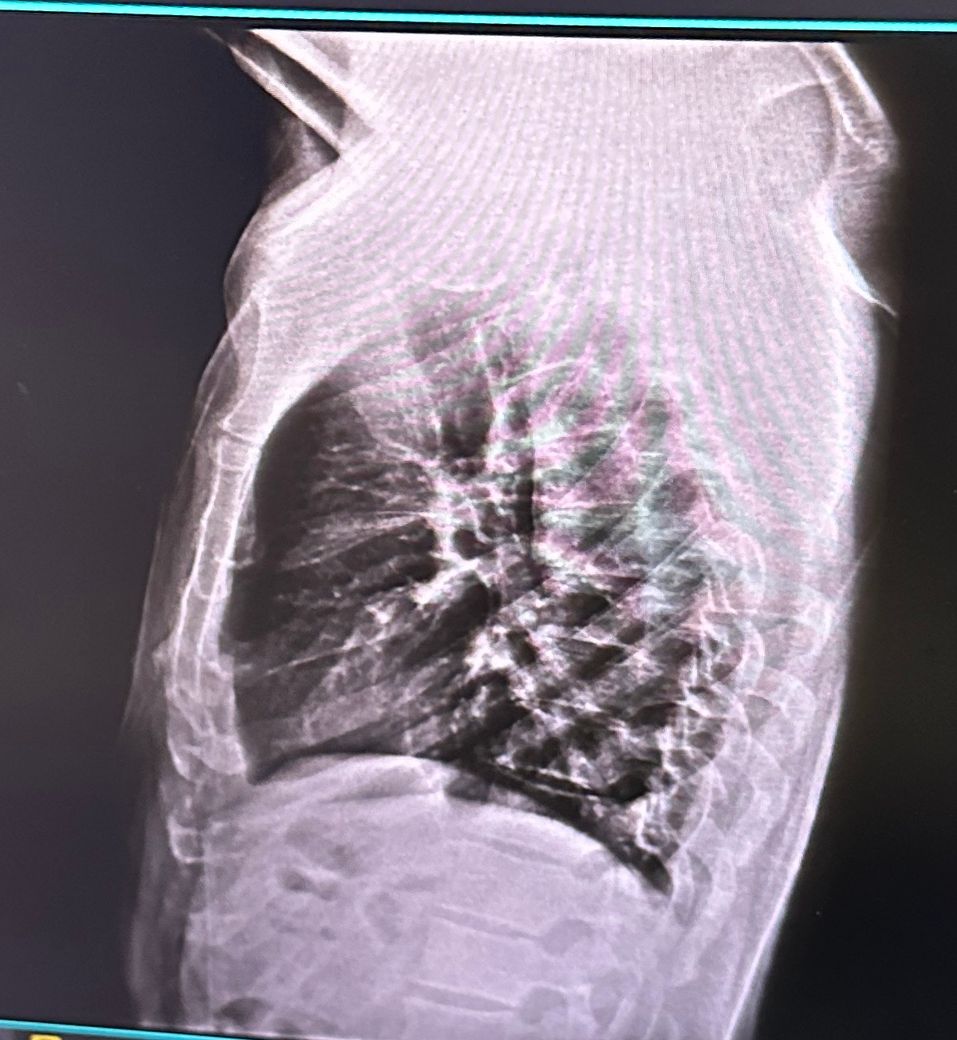

• 1번 째 사진

측만증이 다양한 원인이 있지만 엑스레이 상에서 보아도 측만증이 있어보이긴 합니다. 근데 측만증이라는게 선천적일수도 있고 후천적일 수도 있고 이에따라 치료법이 다르고.. 또한 내가 등이 아프면서 안아프게 하려고 몸을 꼬니까 측만증이 있는것처럼 보일 수 있습니다.

사진상으로 많은걸확인할수는없지만 지금가지고있는 측만증의경우 자세적인문제가있을수있는데요 잠을자거나 휴식을취할때 엎드리거나 만세를하고있는동작은 목어깨나 허리, 몸에 부담을줄수있기때문에 추천하지않습니다